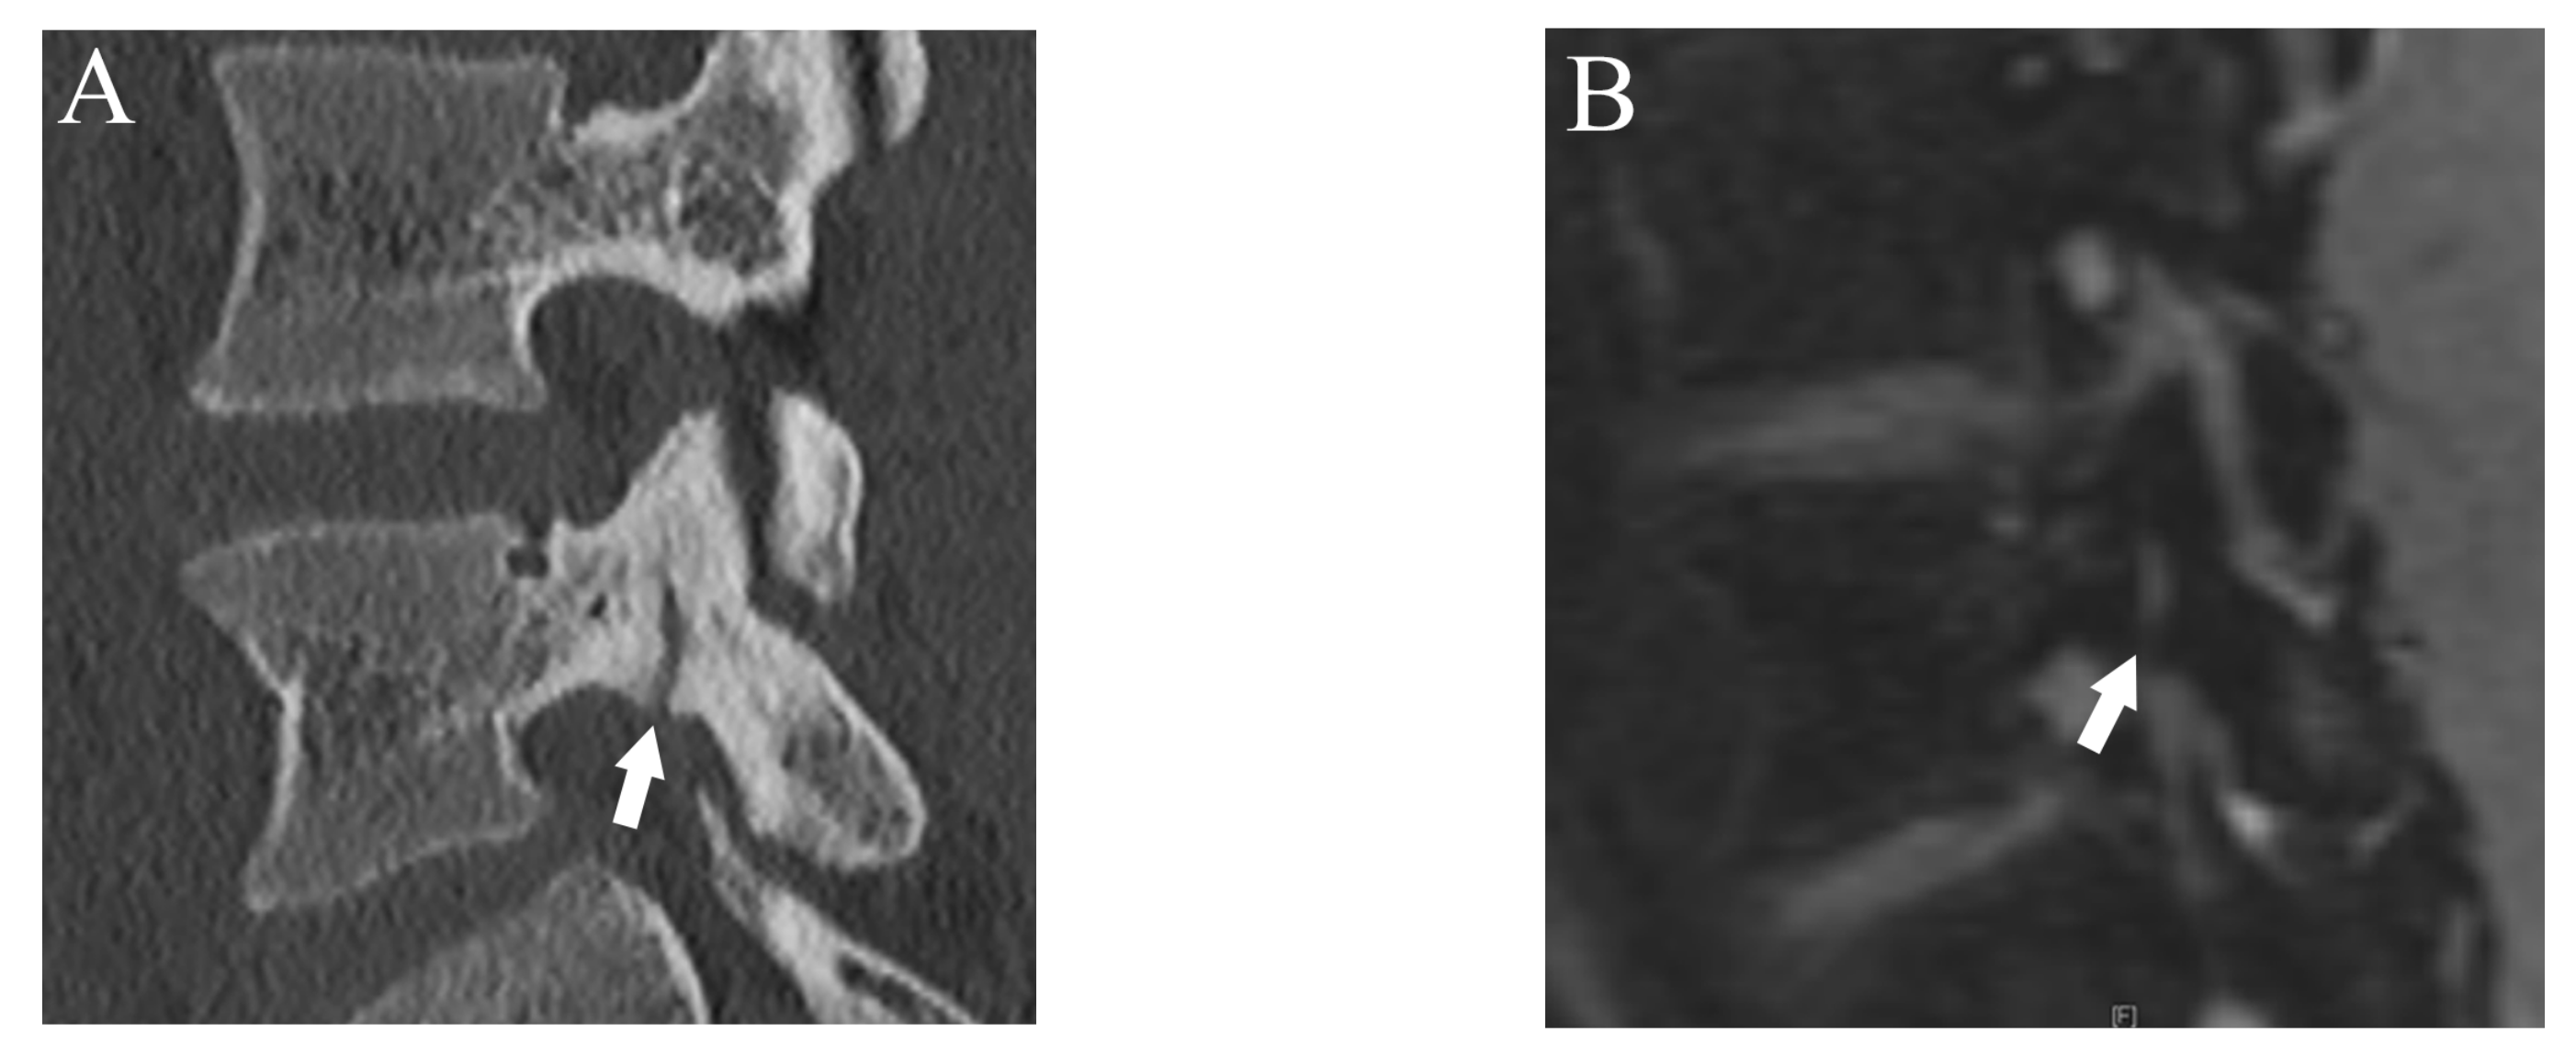

Figure 1.

Representative images of grade 1 fracture. The right pars interarticularis of L3 from a 14-year-old male. (A) Oblique-sagittal CT image showing faint attenuation in the cortex (arrow). (B) The faint attenuation corresponds to slight hyperintensity in the cortex on an oblique-sagittal DESS image (arrow). The window of the image was adjusted to enhance the faint finding. Note the BME in the pedicle (arrowhead). (C) Sagittal STIR image shows BME in the right pedicle of L3 (arrowhead).

After more than a 2-week interval from creating standard references, two readers independently analyzed fractures on T1WI and DESS using the same grading system as used in CT. On MRI, bone resorption (grade 1) can be detected as slight hyperintensity within cortical bone which normally shows homogeneous hypointensity (Figure 1). The fracture line on MRI is delineated as linear hypointensity on T1WI and linear hyperintensity on DESS (Figure 2 and Figure 3). DESS was also used to evaluate the BME binary. Similar to STIR, if there is a high signal at pars interarticularis on DESS, it is considered positive for BME. Consensus results for T1WI, DESS for fracture and DESS for BME were created for statistical analysis.